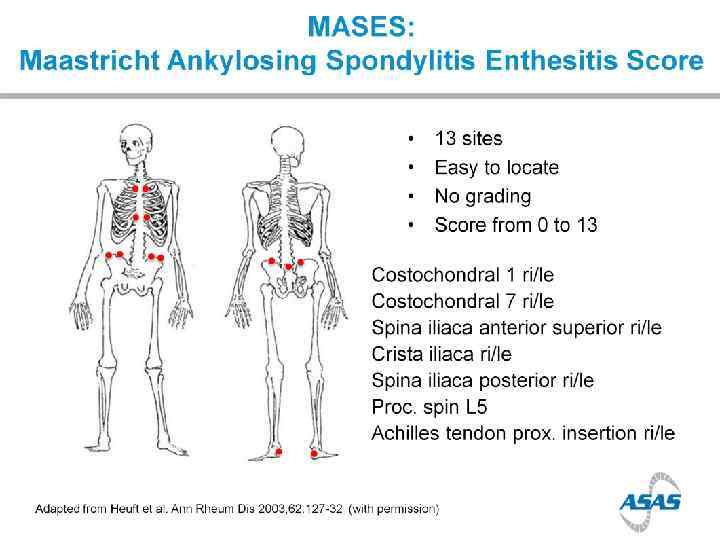

Enthesopathy

Enthesopathy

Enthesopathy